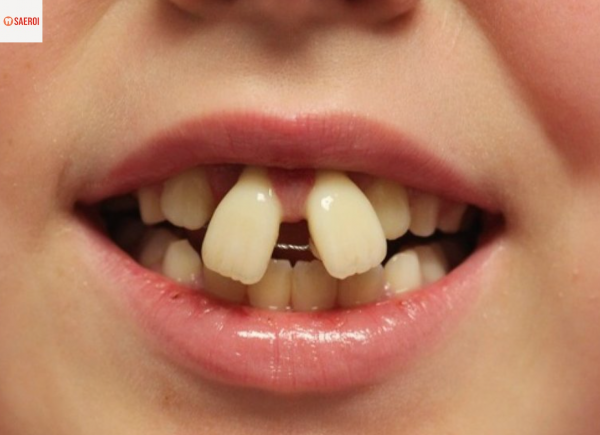

아래 두 사진은

셀프 교정을 시행하고 나타난

부작용들입니다.

벌어진 앞니를 교정하기 위해

고무줄을 양쪽에 끼웠다가

고무줄이 잇몸을 파고들어

잇몸 조직이 파괴된 케이스입니다.

잇몸 지지 조직이 무너져

치아가 돌출된듯한 모습을 하고있습니다.

위와같은 경우 또한

치아 이동의 토크와 벡터 등을 고려하지 않고

장치만 간단히 부착하면 된다고 생각하는 경우에

의도치 않은 매우 심각한 부작용이 생길 수 있습니다.